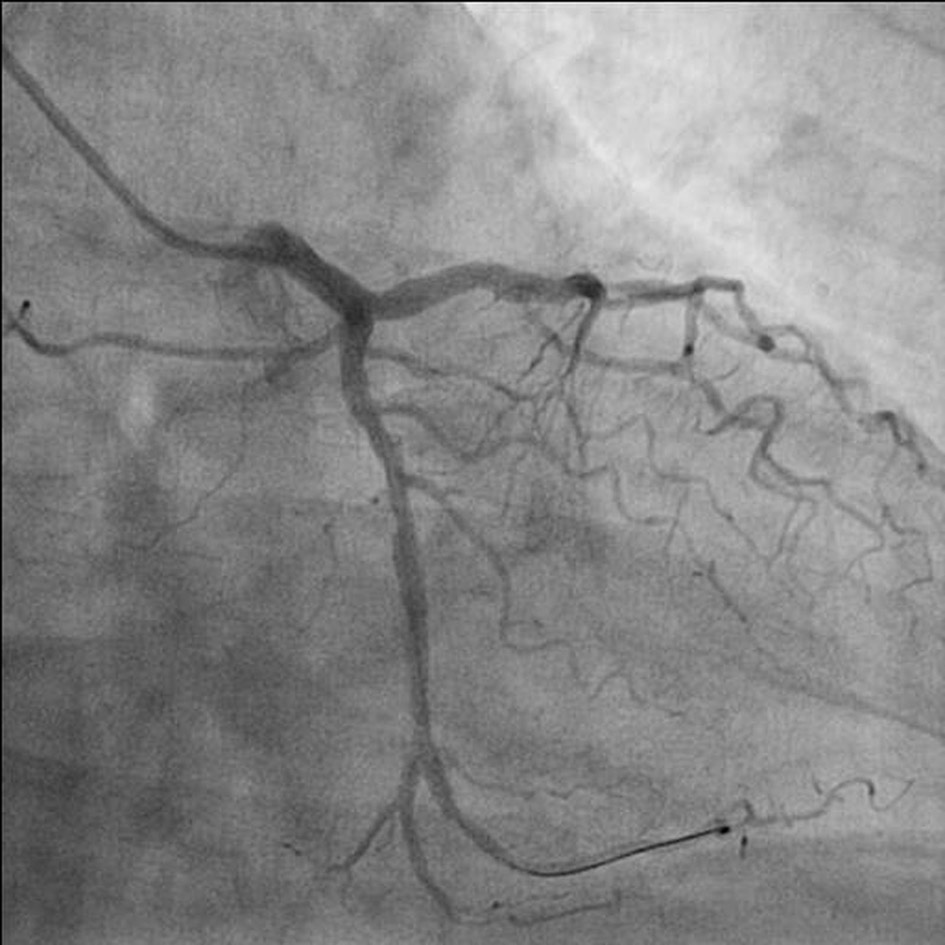

A 41-year-old male with past history of hypertension and dyslipidemia presented with retrosternal chest discomfort and sweating of 2 h duration. His physical examinations and biochemistry were all unremarkable. Electrocardiogram revealed ST elevation in II, III, and aVF with reciprocal changes in I and aVL. Echocardiography revealed mild hypokinesia in left circumflex territory with ejection fraction of 47%. He was taken for primary PCI after proper consent. He was preloaded with prasugrel 60 mg, aspirin 325 mg and atorvastatin 80 mg. Right radial artery was punctured by 21 G needle, 0.021″ guidewires (Avanti transradial kit; Cordis Corp., USA) were inserted and 6-F sheath was placed. After sheath replacement, cocktail containing 200 μg nitroglycerin, 2.5 mg diltiazem, and 2,500 IU unfractioned heparin was injected. While pushing diagnostic catheter, great difficulty was encountered as it was not going forward. Check angiogram revealed double hairpin turn with 360° loop (Fig. 1). First, we tried to negotiate the turn by using 0.035″ hydrophilic wire (Terumo, Japan) but failed. A 0.014″ PTCA guidewire (balance middle weight (BMW)) was used to negotiate the loop which nearly crossed the loop (Fig. 2) and advanced into brachial artery (Fig. 3). Diagnostic catheter was advanced over the wire which negotiated the first hairpin turn of the loop, but refused to budge any further. Another 0.014″ PTCA guidewire (buddy wire) was used by advancing into distal part of brachial artery but could not negotiate the loop. We tried balloon-assisted technique but because of razor effect and 360° loop, it failed (Fig. 4a). We then pushed 1.5 × 10 mm balloon (Sapphire, OrbusNeich, the Netherlands) little further from catheter tip and inflated up to 3 atm pressure by keeping the distal end of the wire into brachial artery. Holding the balloon-wire assembly firm, we advanced the catheter by gently sliding over the inflated balloon, thus negotiating the first turn (Supplementary video 1, www.cardiologyres.org). We deflated the balloon and again pushed little ahead of the catheter. Once again, we inflated the balloon at 3 atm pressure and catheter was advanced by gently sliding over the inflated balloon, thus successfully negotiating the 360° loop overcoming razor effect of tip of diagnostic catheter (Supplementary video 2, www.cardiologyres.org, Fig. 4b). Once crossed the loop, we gently pulled back the entire assembly which straightened the loop and eased the further advancement of the catheter. We pulled out the balloon and the procedure was completed in usual fashion. Coronary angiogram revealed normal left main, left anterior descending artery, right coronary artery arising from left sinus and subtotal occlusion of proximal circumflex artery (Fig. 5a, b). PCI was planned of the culprit artery and 7,000 U of heparin was given further. Since great difficulty was encountered while advancing the diagnostic catheter, we planned intervention through the same diagnostic catheter to cut down the time, to avoid vasospasm while multiple catheter exchange and contrast overload. BMW guidewires 0.014″, 190 cm (Abott, USA) were parked beyond the lesion and were pre-dilated with 2 × 10 mm Minitrak balloon (Abott, USA) to 12 atm (Fig. 5c). It was stented by deploying 2.75 × 21 mm Xience Prime stent (everolimus drug-eluting stent, Abott, USA) up to 13 atm pressure (Fig. 5d) and further post-dilated by 2.75 × 10 mm Minitrak non-compliant balloon up to 20 atm pressure achieving TIMI 3 flow (Figs. 6a, b, c, d, and 7). His symptoms and ECG stabilized. Contrast angiography of the involved segment of the vasculature was performed to rule out any perforation after removal of catheter. Sheath was removed and compression was performed for 2 h with a radial compression device (TR band; Terumo, Inc.) using the “patent haemostasis” protocol. TR band was removed after 2 h of sheath removal and a light pressure bandage was applied which was removed next day. He was discharged on the third day with aspirin 150 mg/day, prasugrel 10 mg/day, atorvastatin 80 mg/day, metoprolol 100 mg/day and ramipril 2.5 mg/day. Patient is doing fine since then with regular follow-up at our institute.

![]() Click for large image | Figure 5. Coronary angiogram revealed normal left main, left anterior descending artery, right coronary artery arising from left sinus and subtotal occlusion of proximal circumflex artery (a, b). Pre-dilatation of lesion by semi compliant balloon (c). Stent (2.75 × 21 mm Xience prime) being deployed (d). |

![]() Click for large image | Figure 6. Post-stenting circumflex artery (a). Post-dilatation of stent by non-compliant balloon (b, c). Post-stenting circumflex artery (d). |

![]() Click for large image | Figure 7. Final TIMI 3 of culprit artery. |